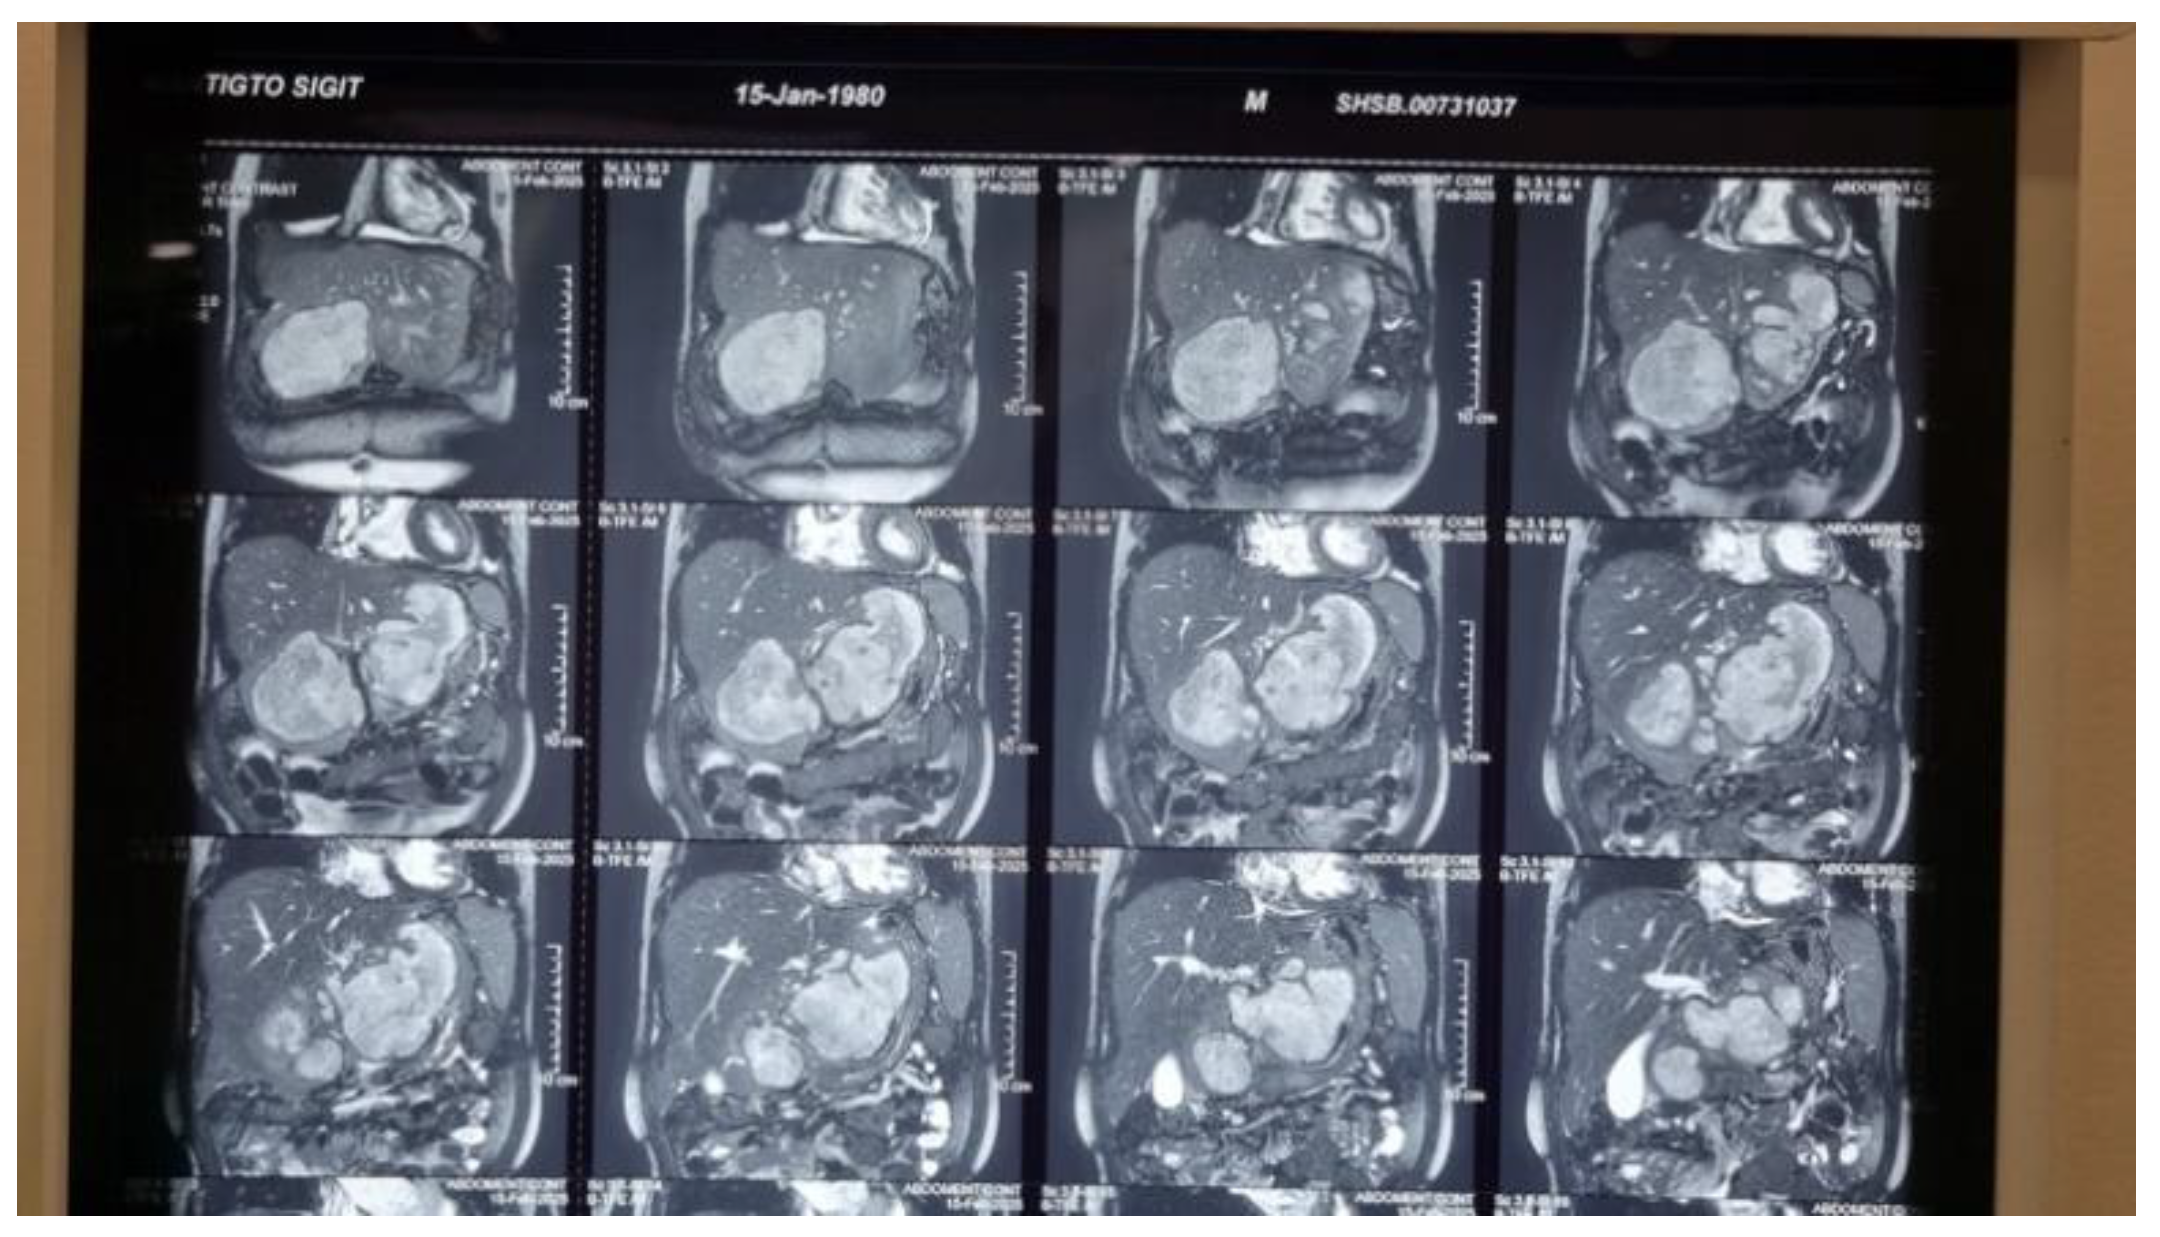

Background: Liver abscesses represent an atypical yet potentially life-threatening complication of bacterial, fungal, protozoal, and helminthic infections. Frequently, the clinical findings associated with liver abscesses are nonspecific, necessitating a reliance on imaging for diagnosis. It is uncommon for a liver abscess to radiographically resemble a malignant liver tumor such as hepatocellular carcinoma (HCC). Here, we present the case of a 45-year-old male who was initially diagnosed with HCC (BCLC C) but was subse-quently found to have a liver abscess following biopsy. Case Presentation: A male patient, 45, presented with stiffness and pain in the right upper abdomen. He complained of nausea and vomiting since 10 days before admission as well. All supportive imaging suggested a diagnosis of HCC. A liver abscess was detected during a biopsy. A liver ultrasound-guided FNAB showcased chronic, suppurative in-flammation with negative acid-fast bacilli on Ziehl-Neelsen staining. The patient sub-sequently developed a complication of middle hepatic artery bleeding and underwent immediate embolization. Discussion: In fact, a liver abscess can be the initial manifestation of HCC. Patients tend to have a poorer prognosis because the diagnosis of a liver abscess often delays the discovery of the underlying HCC. Radiographically, liver abscesses range from well-circumscribed cystic lesions with an enhancing rim to heterogeneously enhancing mass-like lesions, which are sometimes indistinguishable from liver neoplasms. However, it is so scarce that a liver abscess may radiographically mimic HCC. Conclusion: Assessing liver abscess is somewhat complicated since the symptoms vary a lot. Therefore, a correct and exact diagnosis entail a combination of more comprehensive clinical and supporting examinations.